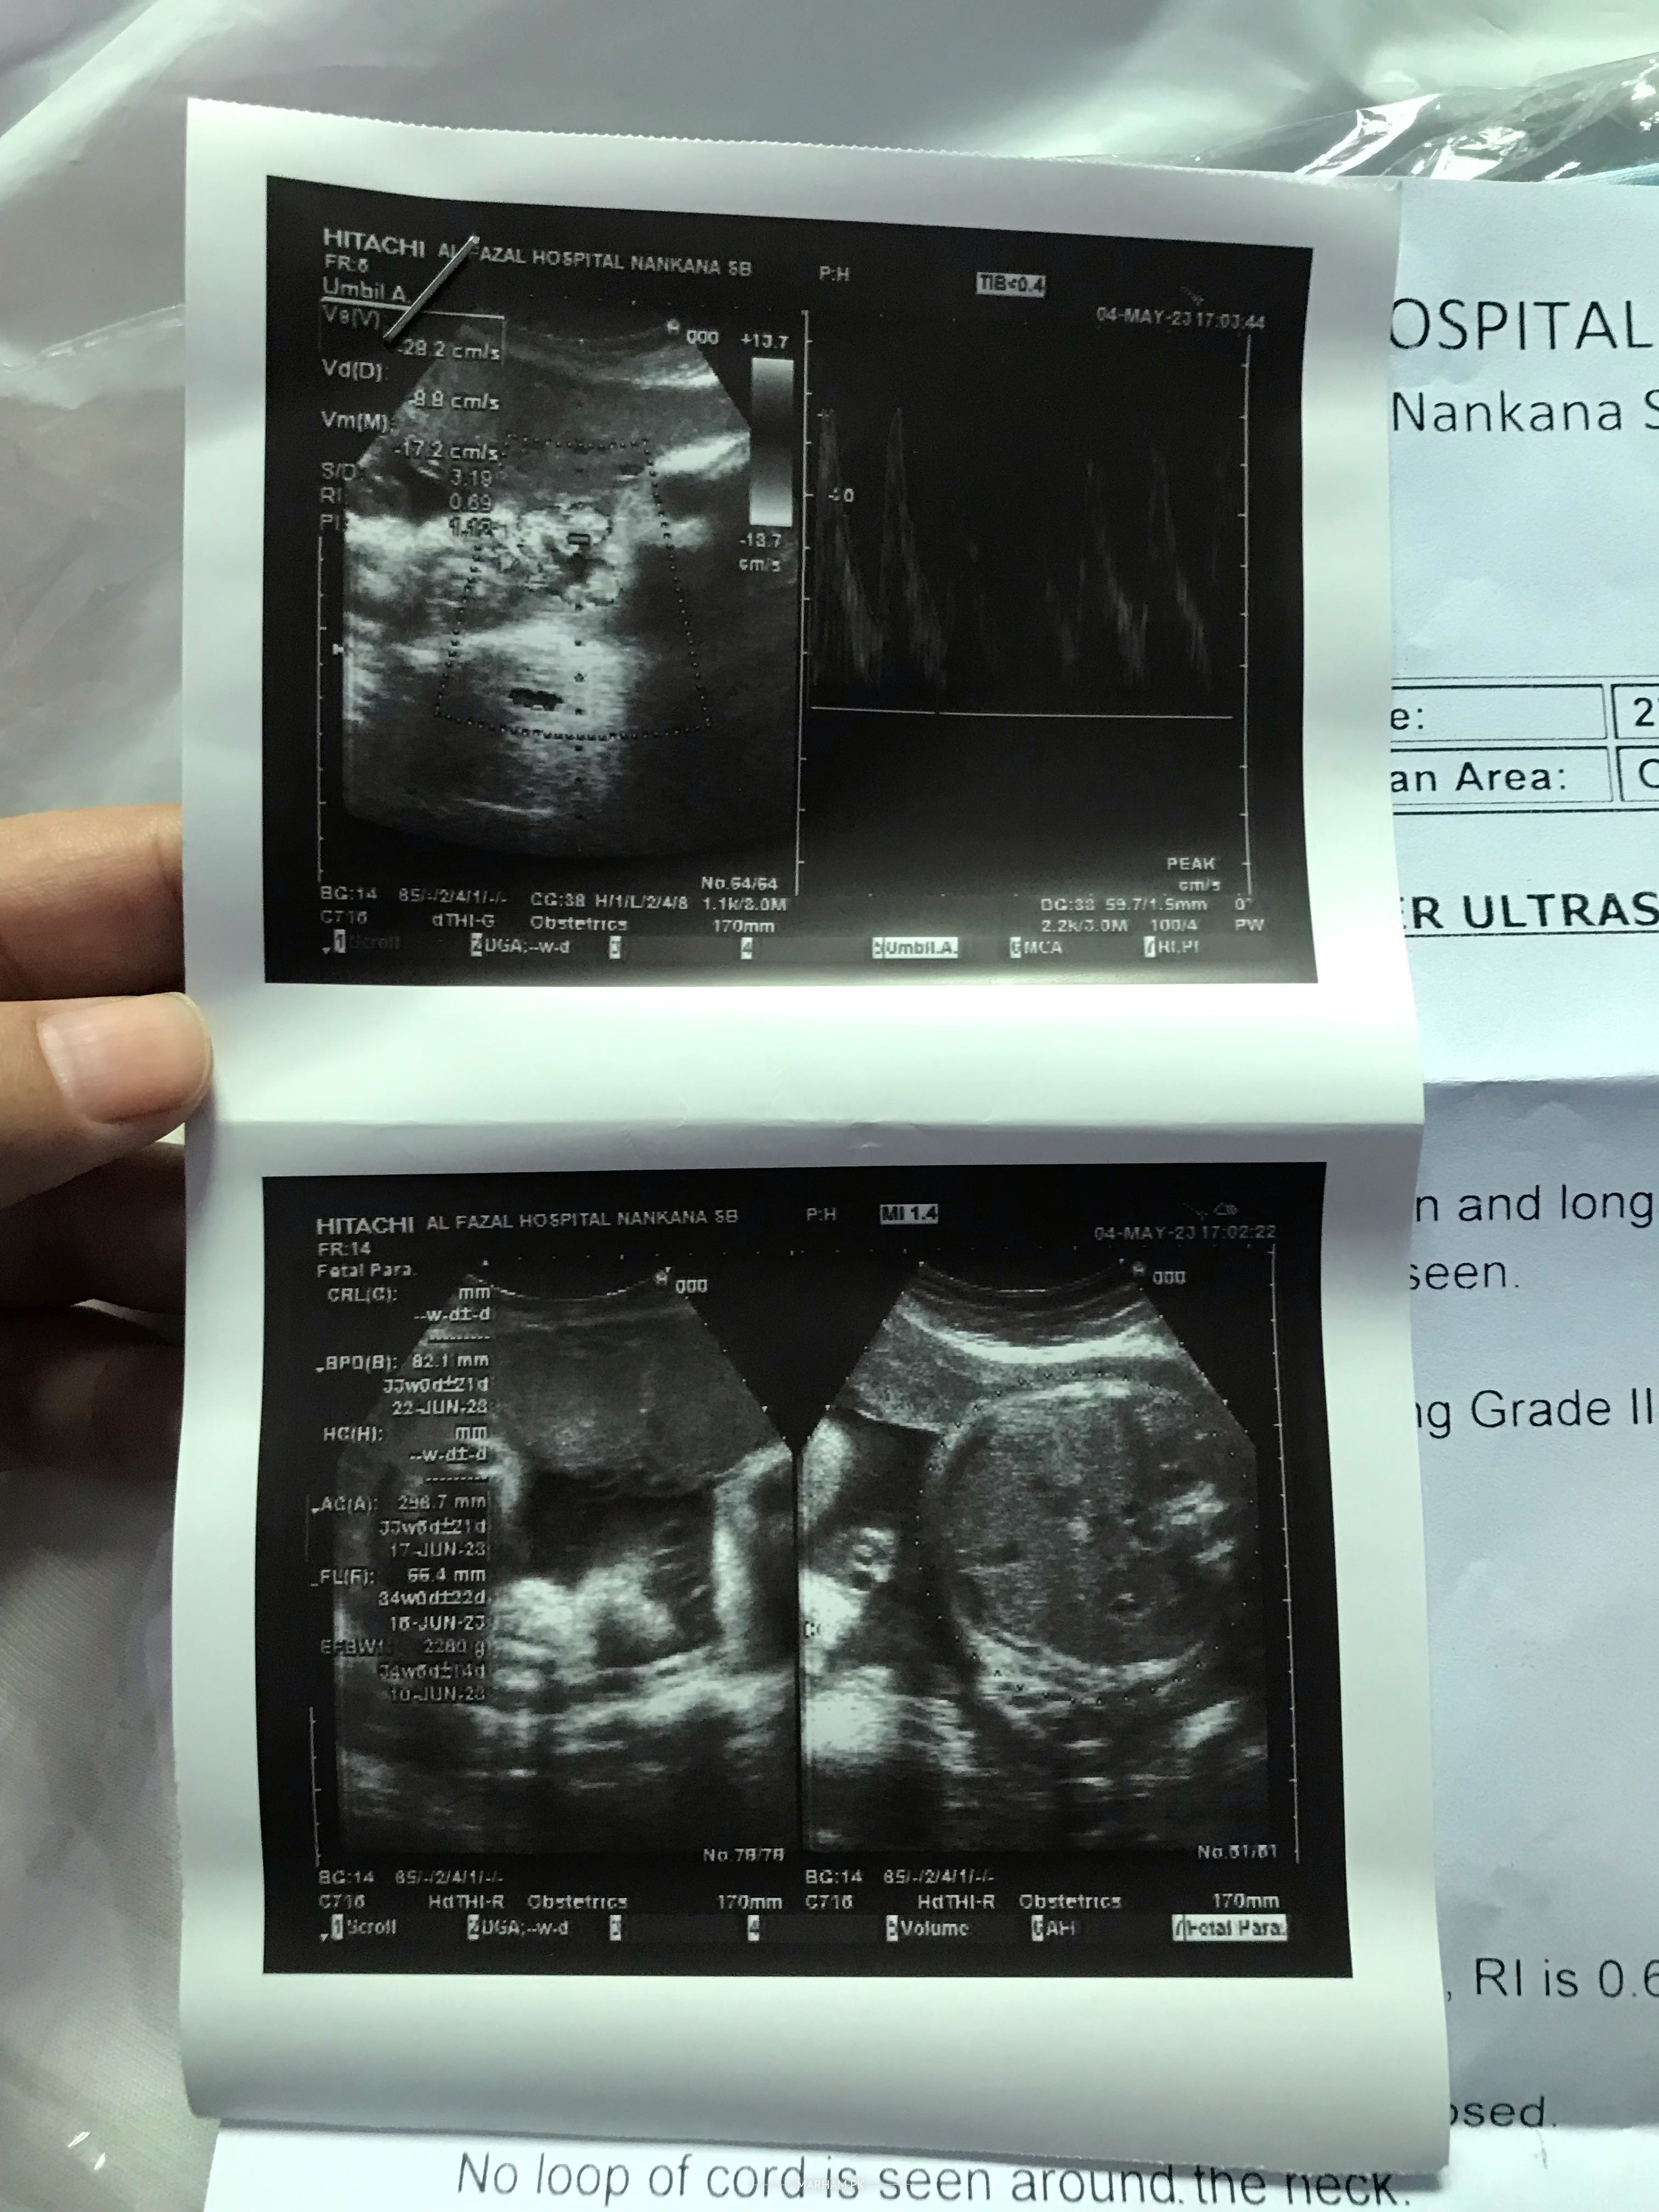

Asslam o alikum doctors mujhy pouchna tha Maine 4 May ko colour Doppler ultrasound karwaya tha us main mery 34 weeks complete thy jo k counting k hisab sy Thek thy Ak 15 May ko doctor ko check karwaya hai to wo keh Rahi hain ap k 32 weeks hain abi ye Kyn itna difference aa raha jb k inko Maine 2 weeks pehly bhi check karwaya tha tab bhi mery 32 weeks thy or Aj bhi wo keh Rahi thi scanning main itna difference aa jata hai Kya ye normal hai ???Report attach ki hain plz check Kar k btaye ga

dopper is normal range. follow your doc . one week ka diffence is normal

2 week difference is normal .Doppler also normal u can repeat after 2 weeks with same doctor